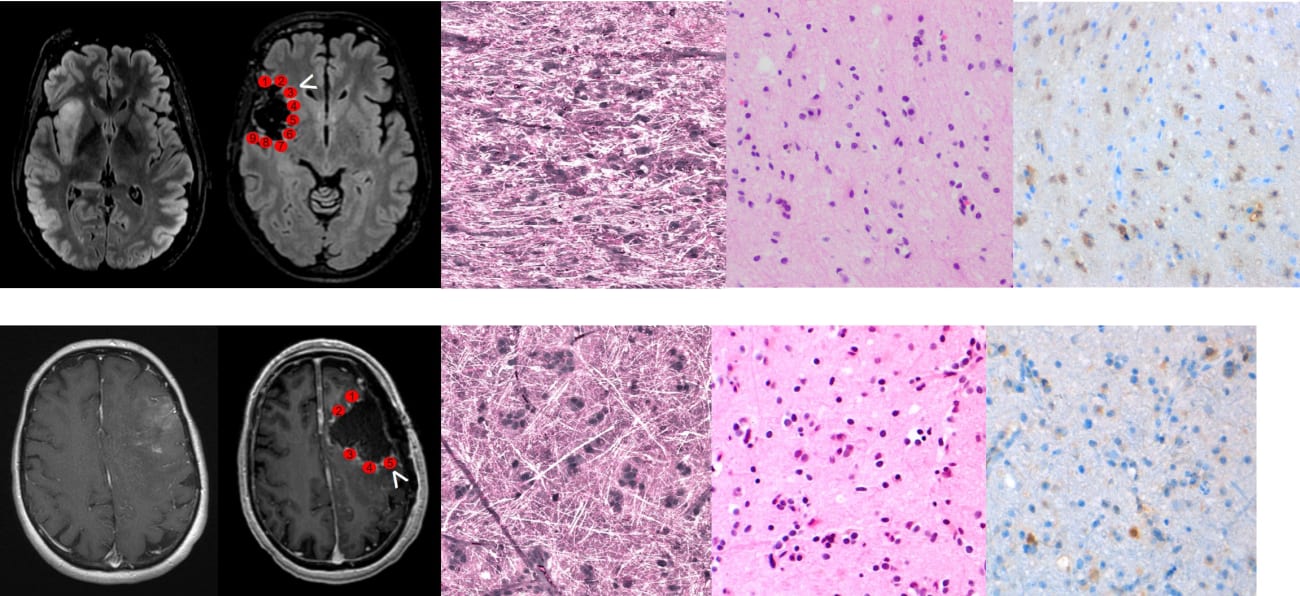

In a recently published study, the UC San Francisco Brain Tumor Center team validated a novel optical imaging technique called stimulated Raman histology (SRH) for rapid, intraoperative detection of glioma infiltration at the tumor margin. This method yields images within minutes for microscopic detection of residual tumor cells—information that can help guide decisions on the extent of resection and improve patient survival rates.

Identification of tumor cells on a microscopic level is normally a time- and labor-intensive process, not feasible for intraoperative rapid detection. SRH is a nondestructive, rapid, label-free technique that provides imaging of unprocessed surgical tissues at microscopic resolutions.

Researchers found agreement when comparing SRH images with IHC and H&E stains

When comparing the SRH images of the 179 margin samples to images of the same samples produced using standard microscopic detection methods, the UCSF researchers found excellent agreement with immunohistochemistry (IHC) and hematoxylin and eosin (H&E) stains. SRH imaging can generate pseudo-H&E images within minutes, allowing for microscopic-level identification of residual tumor cells during surgery. Not previously validated in the intraoperative setting, this innovative technique has the potential to significantly increase the amount of tumor that can be removed and therefore improve survival rates for patients with brain tumors.